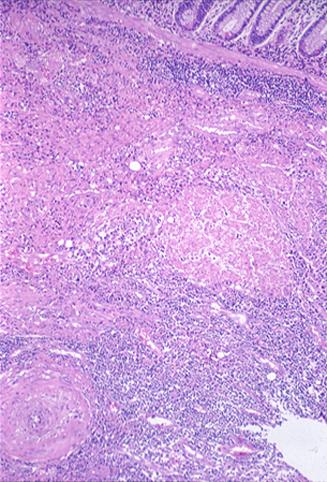

악성 림프종과의 감별진단이 곤란하였던 회장말단부의 소장 아니사키스 절제예

기생충질환/아니사키스

소장/회장

마이크로